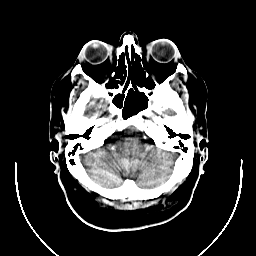

CT Study #1 -- Slice #5

[Home][Help][Clinical][Tour 1] Slice 5